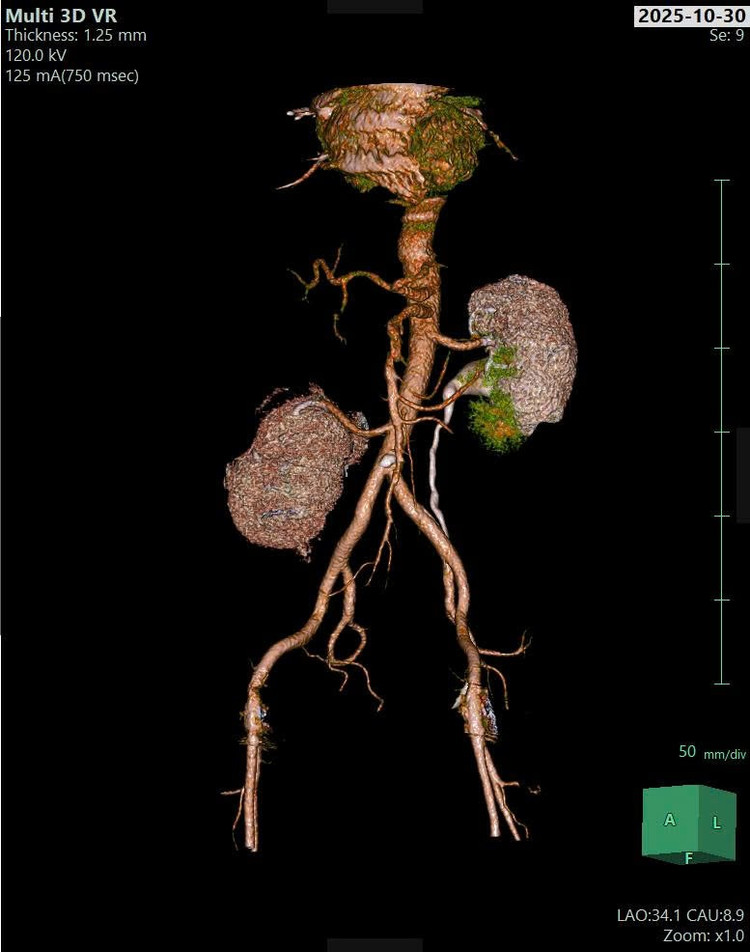

Các bác sĩ đã nhanh chóng thực hiện các cận lâm sàng cần thiết. Kết quả chụp CT-Scanner ổ bụng ghi nhận viêm thận – bể thận phải, thận phải lạc chỗ và giãn đài bể thận trái.

Hình ảnh chụp Cắt lớp vi tính có tiêm thuốc cản quang: Thận phải lạc chỗ, nhu mô thận phải ngấm thải thuốc kém hơn thận trái, bể thận xoay ngoài, nhu mô thận có hình ảnh các ổ không ngấm thuốc (quan sát rõ ở các thì tĩnh mạch và thì muộn) - Ảnh BVCC

Hình ảnh chụp Cắt lớp vi tính có tiêm thuốc cản quang - Ảnh BVCC